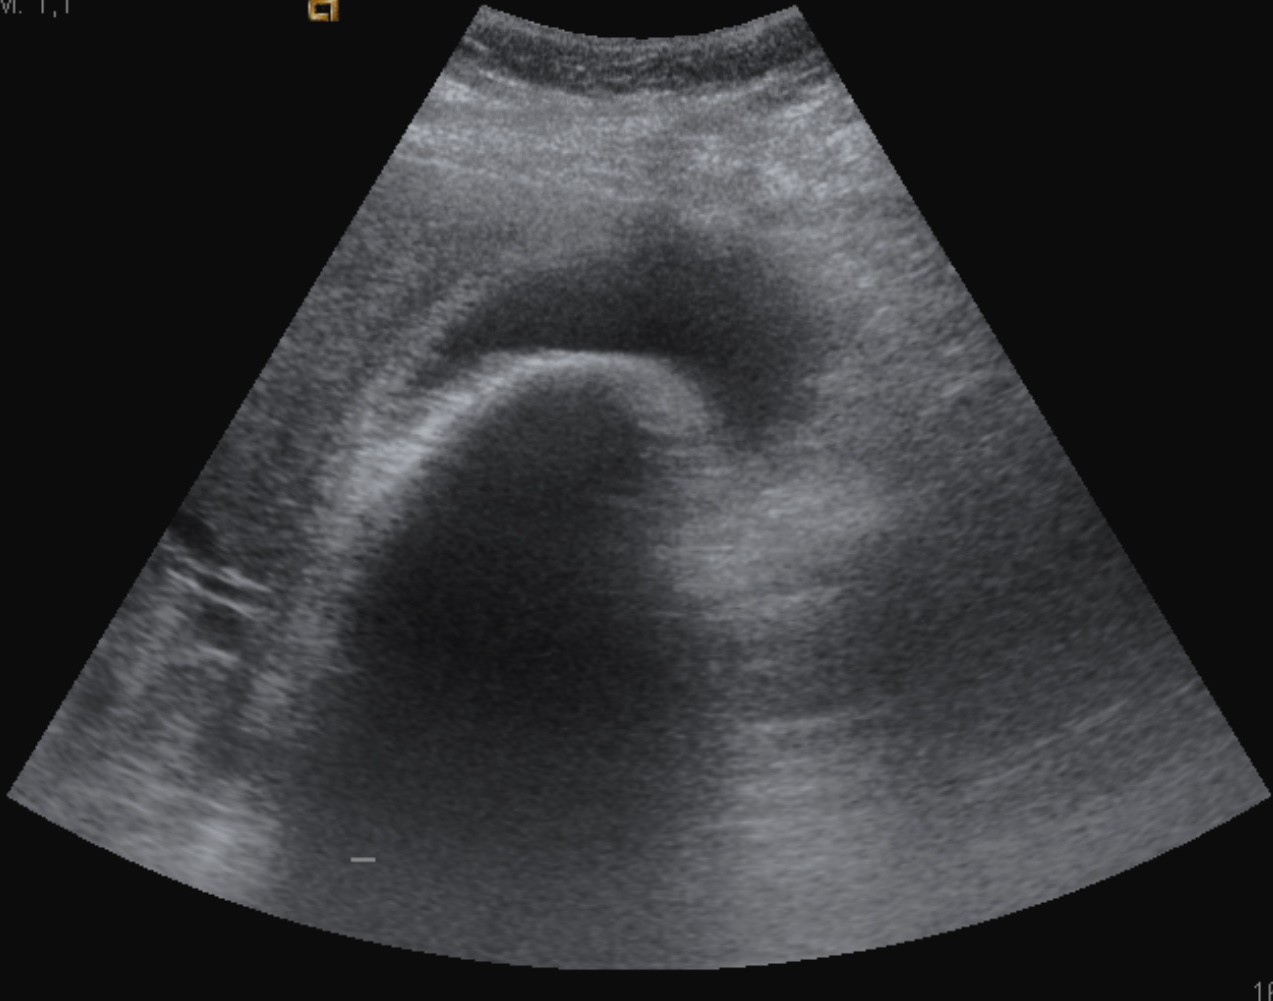

Se realiza ecografía abdominal:

Con estos hallazgos ecográficos podemos concluir que el paciente presenta una COLECISTITIS AGUDA.

Es la técnica de elección para el diagnóstico cuando se sospecha colecistitis (S y E > 95%, Robert et al.).

Criterios ecográficos de colecistitis (No existe consenso generalizado):

– Murphy ecográfico positivo y colelitiasis: es la combinación de signos ecográficos más predictiva de colecistitis aguda (VPP 92%). Puede resultar difícil observa la litiasis si ésta se localiza en el conducto cístico o en el cuello de la vesícula. Con engrosamiento mural el VPP aumenta al 94%)

- Engrosamiento de la pared vesicular (>4mm) en ausencia de enfermedad hepática crónica, ascitis o insuficiencia cardiaca (el VPP asciende al 94%).

- Líquido perivesicular.

- Vesícula biliar distendida.

- Presencia de barro o material ecogénico en el interior de la vesícula.

Según la guía de Tokyo, el diagnóstico de colecistitis litiásica aguda puede hacerse cuando están presentes al mismo tiempo los siguientes hallazgos: engrosamiento de la pared vesicular mayor de 5 mm, líquido pericolecístico y Murphy ecográfico positivo. Otros signos son distensión vesicular, litiasis biliar, barro o material ecogénico biliar y gas en la pared. Sin embargo, debido a diferencias entre datos de frecuencia de sensibilidad y especificidad de los hallazgos individuales, el diagnóstico debe ser hecho a partir del análisis juicioso de los hallazgos individuales.